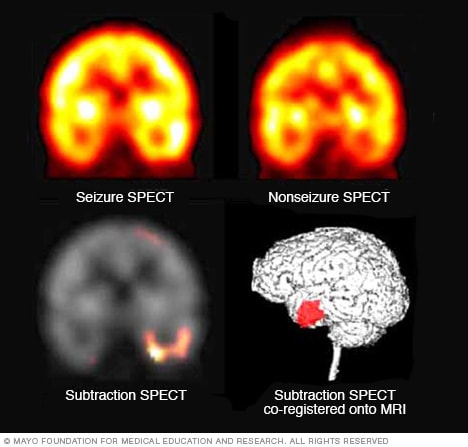

Surgery is most commonly done when tests show that your seizures originate in a small, well-defined area of your brain that doesn't interfere with vital functions such as speech, language, motor function, vision or hearing. In surgery, your doctor removes the area of your brain that's causing the seizures.

Potential future treatments

Researchers are studying deep brain stimulation as a potential treatment for epilepsy. In deep brain stimulation, surgeons implant electrodes into a specific part of your brain. The electrodes are connected to a generator implanted in your chest or the skull that sends electrical pulses to your brain and may reduce your seizures.

Researchers are also studying stereotactic radiosurgery as a potential treatment for some types of epilepsy. In this procedure, doctors direct radiation at the specific area of your brain that is causing your seizure.